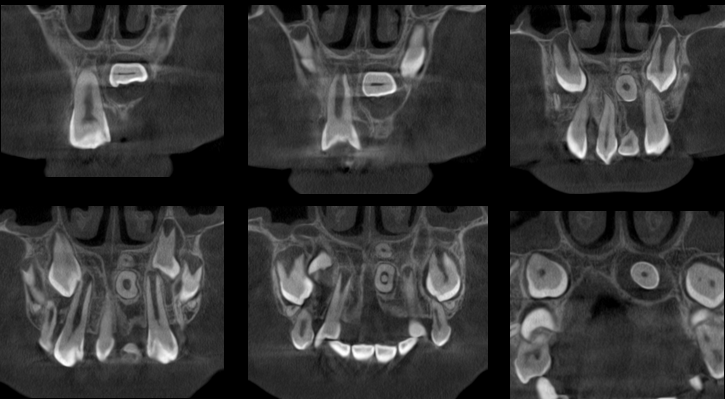

A la evaluación de la tomografía computarizada se puede observar con más claridad el supernumerario denominado “A” de forma rudimentaria que se encuentra por palatino de la pieza 11 y que contacto con la cortical del agujero nasopalatino, asimismo observamos la pieza 21 con la porción coronaria en contacto con la tabla ósea vestibular adelgazándola; finalmente y como hallazgo imagenológico se encontró un segundo supernumerario denominado “B” que se localiza cefálico a la pieza 21 también en posición transversal pero con la porción coronaria en contacto con la tabla ósea palatina y el piso de fosa nasal y finalmente el tercio apical se e en contacto con

la región cervical de la pieza 21.

CORTES TANGENCIALES